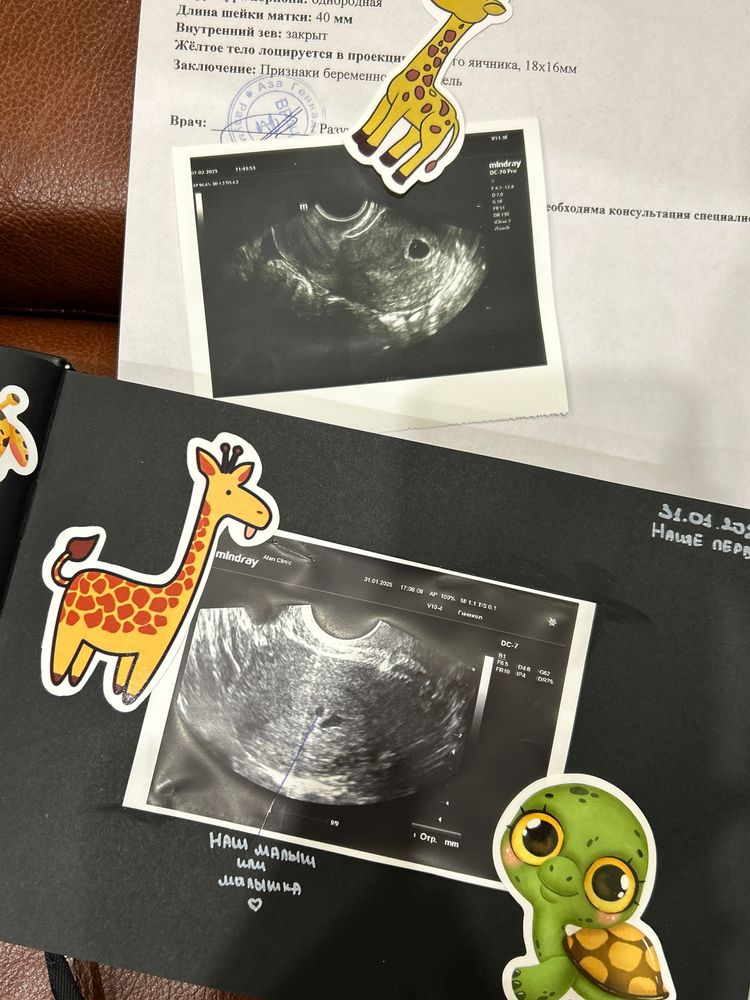

cherry, мес были 3.12 овуляция 12.01 тест начал полость 22.01

cherry, даа и хгч сдавала, судя по овуляции срок 5,5 акушерских

3,5 эмбриональных

У меня в 5 недель акушерских только пя было 3,4мм, сейчас на 6 неделе 11,9мм и жм 2,7мм, но по узи сказали 5 недель только, видимо из-за поздней О

У меня в этот раз в 5,5 ничего не увидели, а в 7.5 уже все было. В прошлые беременности раньше 7 недель не ходила на узи

У меня плодное яйцо 8 мм. Была на УЗИ на 5 нелеле ровно. Позвали на 7 неделе. Это вот в понедельник будет. Тогда и малыш будет и сердечко и мешочек. Не переживайте у некоторых на 5 неделе ПЯ меньше бывает даже.

У меня на 5,5 не было видно ЖМ. Через неделю уже все увидели на УЗИ.

Все отлично) У меня в 6 нед было только ПЯ 7 мм, через недельку уже ЖМ и эмбрион.